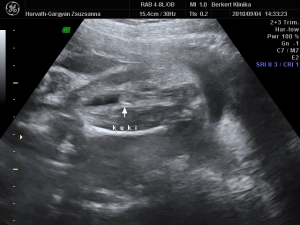

nagyon jó eltelt a szombatunk a drága férjemmel, későn keltünk, egy kis fincsi sült császár szalonnás reggeli tükör tojással...aztán takarítás, csodaszép idő volt ma...2-re mentünk a 4D-s uh-ra :!: :wink:

Valami fantasztikus volt :lol: annyira jól éreztük magunkat, Cipike annyira kis izgága babó, hogy alig lehetett követni mikor merre van, de sikerültek a képek és a DVD-s...egyszerűen nem tudunk vele betelni, már 2-szer megnéztük és még mindig ámulunk és bámulunk :!: :roll: :wink: Sztem az arca totál rám hasonlít, apácska el is volt keseredve :roll: :wink:

Minden a legnagyobb rendben van Cipikével, már 1140 g és csodaszép kis kukis :!: :wink:

És egy pár kép a 4D-ről...

Kép ARC

Kép KUKI, oda is van írva, csak a kicsinyítés miatt nem nagyon lehet elolvasni :!: :roll: :wink:

Kép MOSOLY